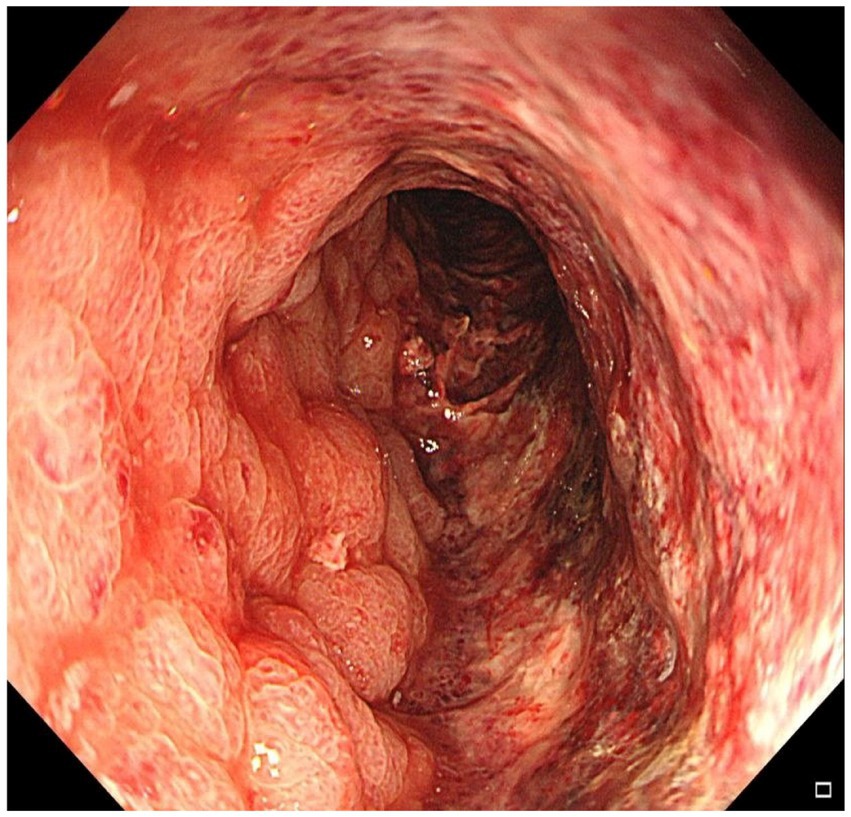

Initial colonoscopy performed at a local hospital revealed circumferential mucosal congestion, edema, and erosion in the sigmoid colon (15–30 cm from the anal verge), a visible anastomosis site was noted at 35 cm from the anal verge. Histopathology showed chronic inflammation with vascular dilation. A preliminary diagnosis of ischemic colitis was made. He was treated with bowel rest, intravenous fluids, mesalazine, and antibiotics, but his condition worsened—abdominal pain intensified (VAS 7–9), and bloody diarrhea increased to 30–40 episodes per day. He was subsequently referred to our hospital for further evaluation. On admission, physical examination revealed abdominal distension, lower abdominal tenderness, and marked rebound pain. Laboratory investigations showed leukocytosis [WBC 10.87 × 10⁹/L (3.5–9.5)], elevated D-dimer [1.8 mg/L FEU (reference <0.5 mg/L FEU)], hyponatremia [Na+ 131 mmol/L (135–145)], and hypokalemia [K+ 3.2 mmol/L (3.5–5.1)]. Repeat colonoscopy demonstrated diffusely swollen, purple mucosa extending from 15 to 30 cm above the anal verge (Figure 1). Biopsy again revealed chronic inflammation with mucosal necrosis. Serological tests for autoimmune diseases (ANA, ANCA, anticardiolipin antibodies) and infectious pathogens (CMV-IgM, Clostridium difficile) were all negative.

Figure 1

Colonoscopy demonstrated diffusely edematous and violaceous mucosa extending from 15 cm to 30 cm above the anal verge, with friability and granular appearance.